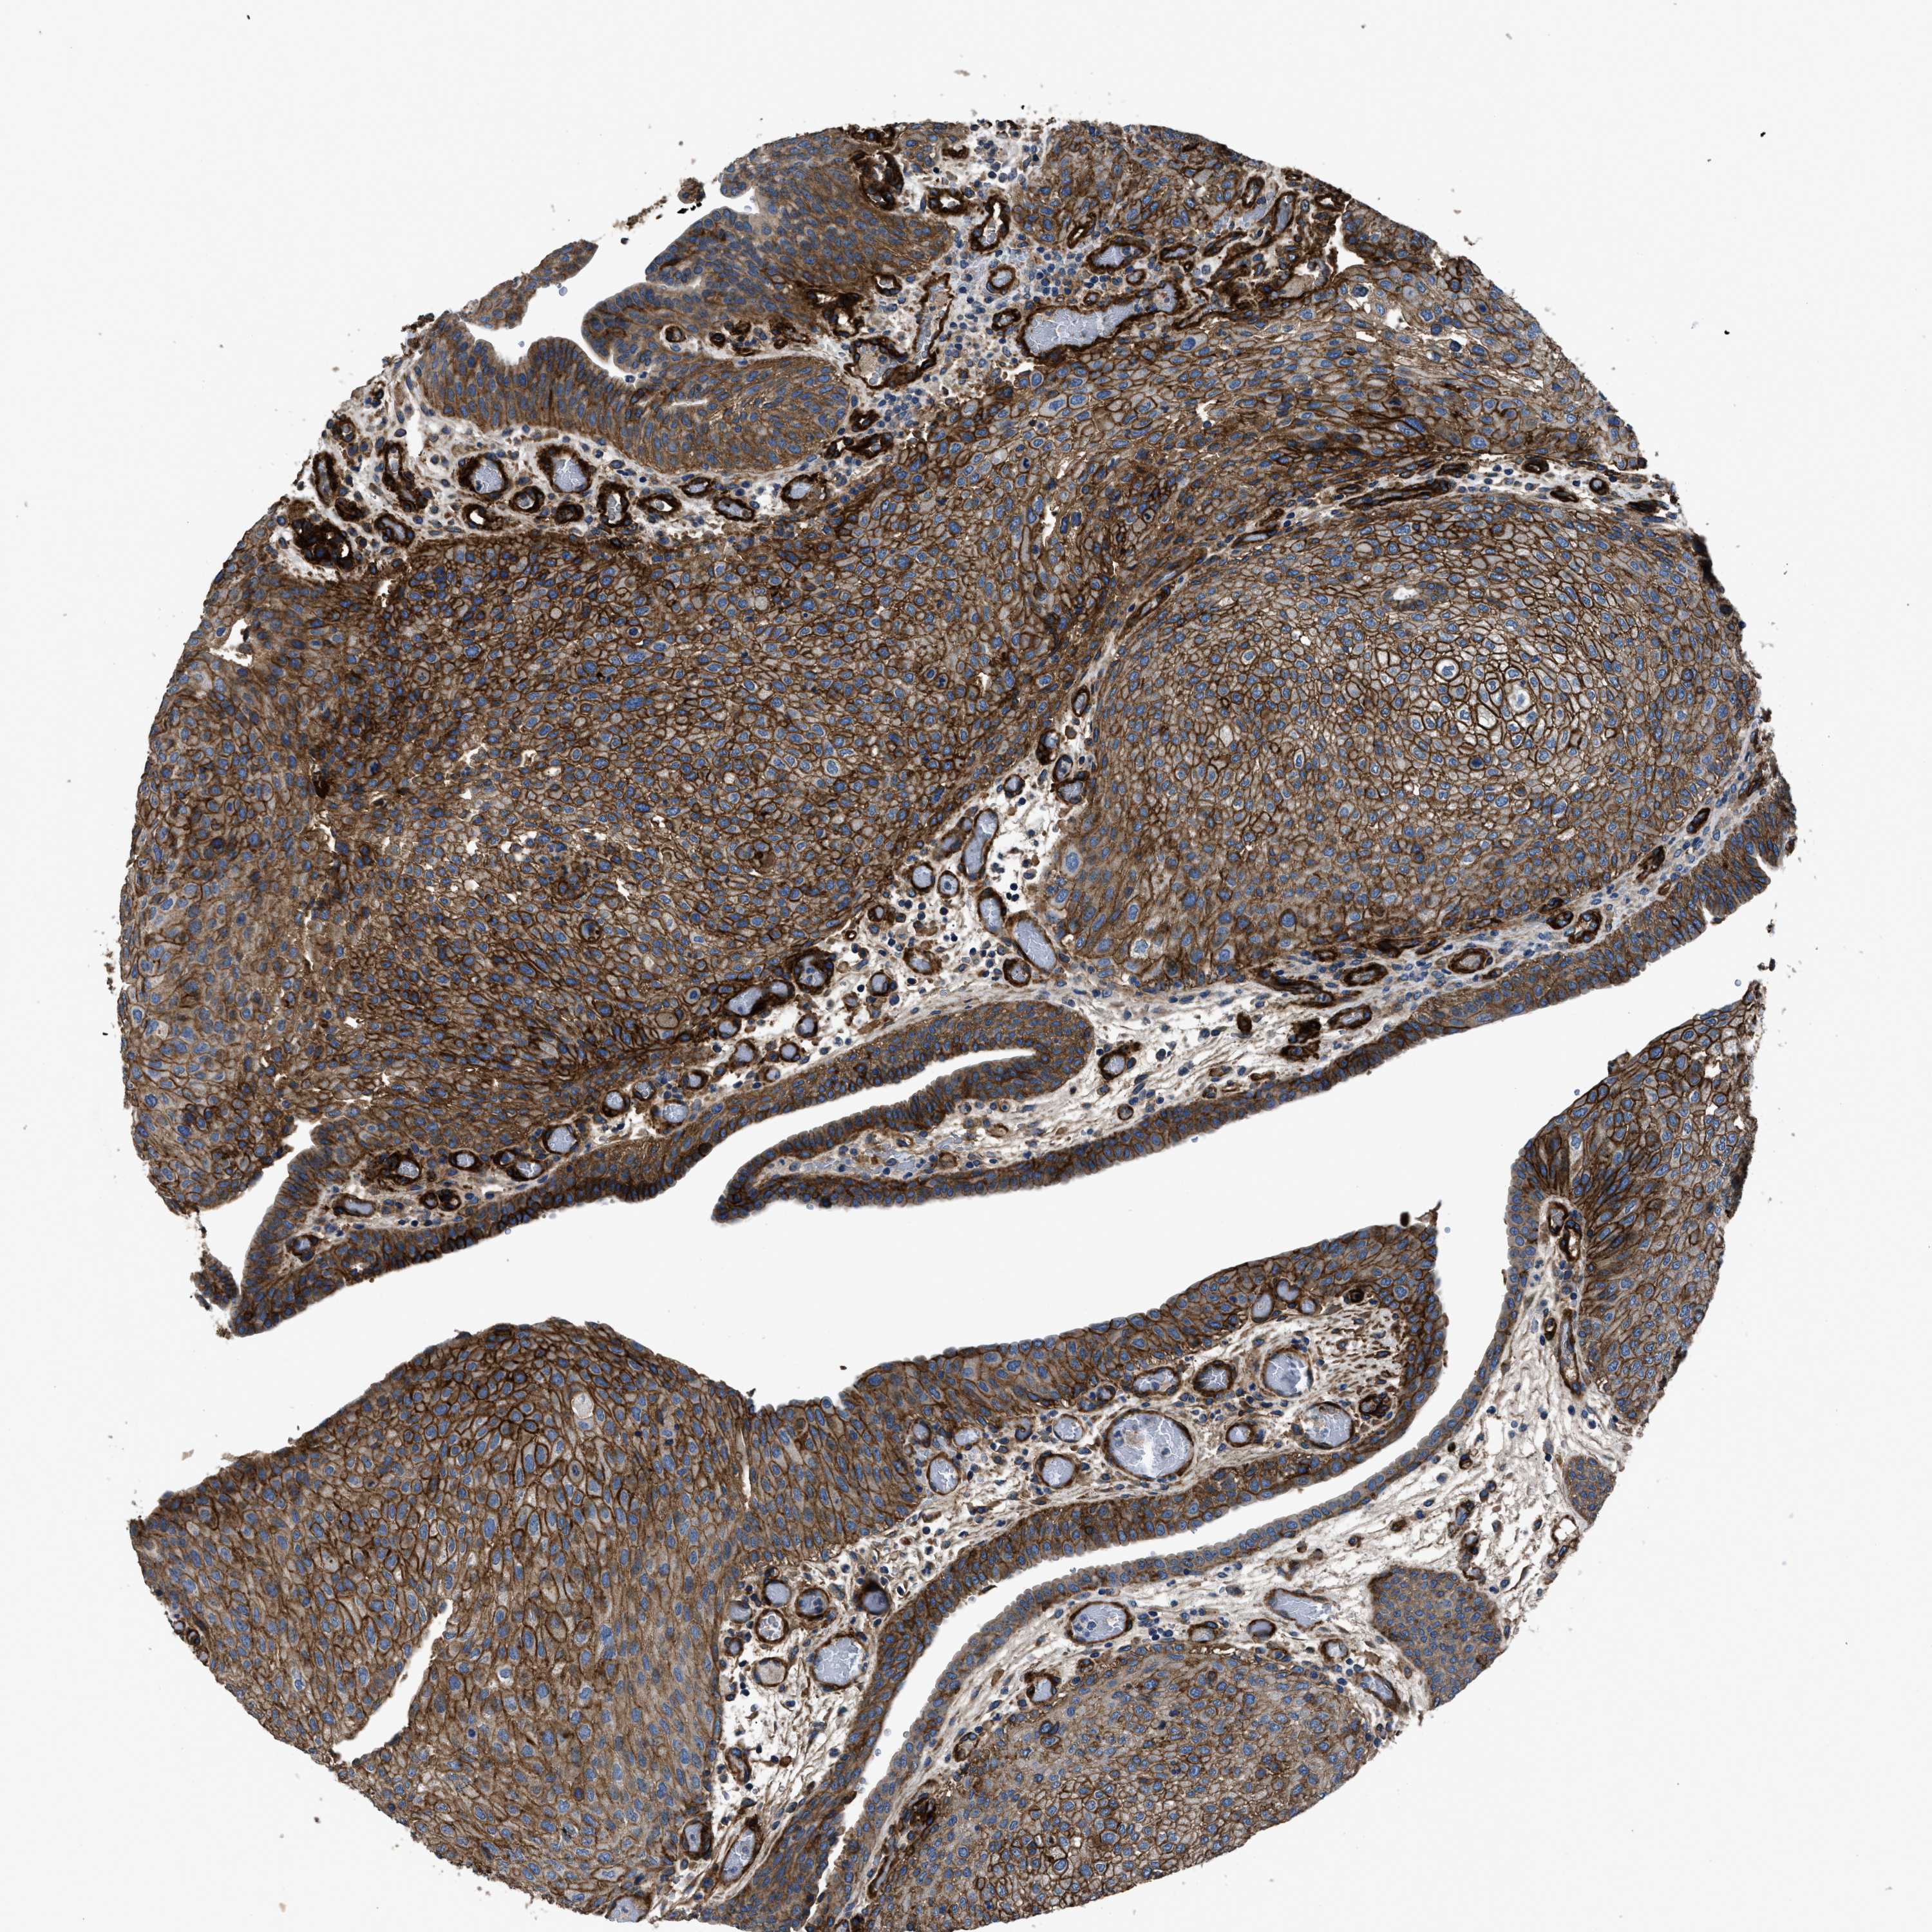

UROTHELIAL CANCER - Protein expressioni

A mouse-over function shows sample information and annotation data. Click on an image to view it in a full screen mode. Samples can be filtered based on level of antibody staining by selecting one or several of the following categories: high, medium, low and not detected. The assay and annotation is described here.

Note that samples used for immunohistochemistry by the Human Protein Atlas do not correspond to samples in the TCGA dataset.

Antibody stainingi

Antibody staining in the annotated cell types in the current human tissue is reported as not detected, low, medium, or high, based on conventional immunohistochemistry profiling in selected tissues. This score is based on the combination of the staining intensity and fraction of stained cells.

Each image is clickable and will lead to virtual microscopy that enables deeper exploration of all samples and also displays staining intensity scores, fraction scores and subcellular localization as well as patient and tissue information for each sample.

Antibody HPA009285

Antibody HPA017139

Antibody CAB017826

Urothelial carcinoma, Low grade

Urothelial carcinoma, High grade